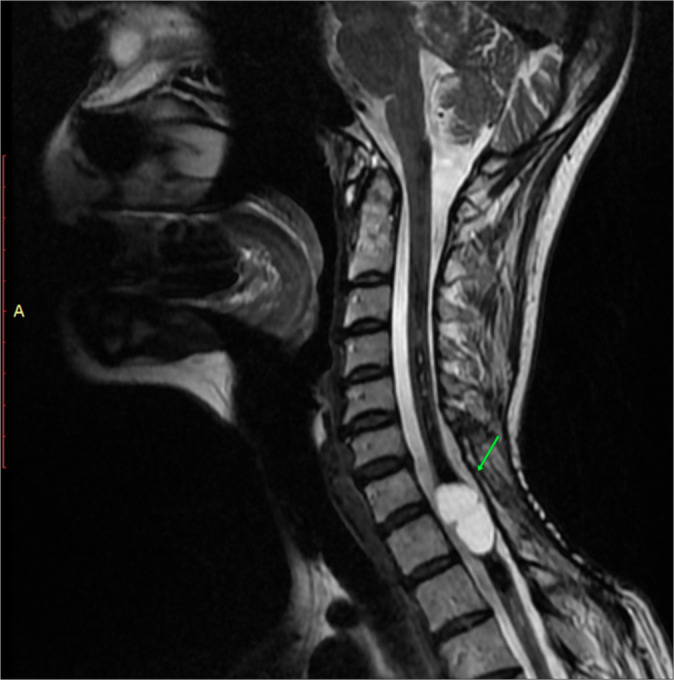

Syringomyelia is a rare condition characterized by the formation of a fluid-filled cyst within the spinal cord, leading to myelopathy. In addition, the pathological enlargement of the central canal is referred to as hydromyelia or cleft-like syrinx. We present a case of idiopathic syringomyelia and hematomyelia in a 50-year-old female patient with a 5-year follow-up on her disease progression. Magnetic resonance imaging (MRI) images revealed low-signal intensity on T1 and high-signal intensity on T2, with elevated hemorrhagic signal intensity on T1 and low peripheral signal intensity on T2. A fluid-filled lesion measuring 12 × 36 mm was observed between the C7 and Th3 vertebrae, with separation from some of the detailed components. No contrast enhancement was noted following IV contrast administration. Based on the MRI findings, a diagnosis consistent with giant hemorrhagic syringomyelia was established. Subsequently, a neurosurgical intervention was performed, resulting in a reduction in the size of the syringomyelia and a moderate improvement in the patient's symptom profile.